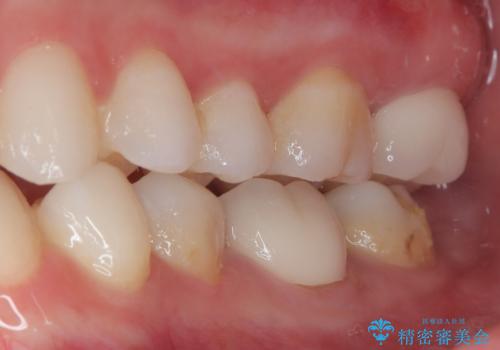

歯がしみることがなくなったと大変喜んでいただけました。

適合もよく、機能的に問題もなく、見た目も満足されていました。